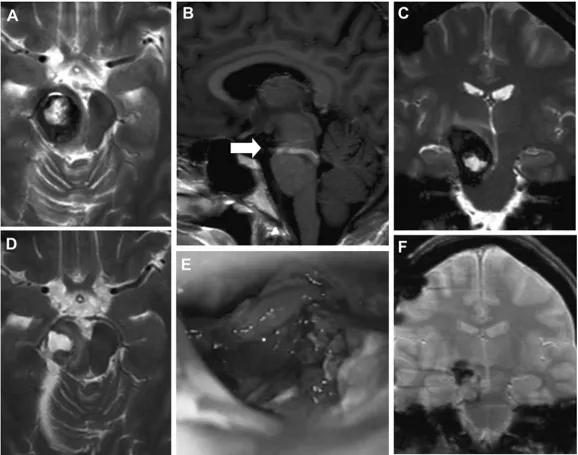

术后一周内患者临床症状好转,并于妊娠40周及时产下一名健康女婴。分娩两个月后,陈女士出现左侧面部麻痹,和脑桥切除腔再出血,经MRI证实。与最初的图像相比,在脑桥区发现一个脑干海绵状血管瘤残余,更多的是背侧和下方(图3)。T1核磁共振造影(考虑到胎儿安全,未在妊娠期间进行)显示竟是一个巨大的发育性静脉异常(DVA)。这次手术是通过乙状窦后幕下小脑上入路进行的,全部切除了脑桥的脑海绵状血管瘤。术后,陈女士症状改善,第二次手术后一年,陈女士状态恢复的非常好,回归到正常生活。

图3:患者1分娩后的术前MRI(A–C)、术中视图(D)和术后MRI(E和F):轴向(A)、矢状面(B)和冠状面(C)MRI平面显示脑干海绵状血管瘤病变的残余和较大的DVA(箭头,B)。术中显微镜观察(D)显示手术腔和海绵状血管瘤残留(星号)。